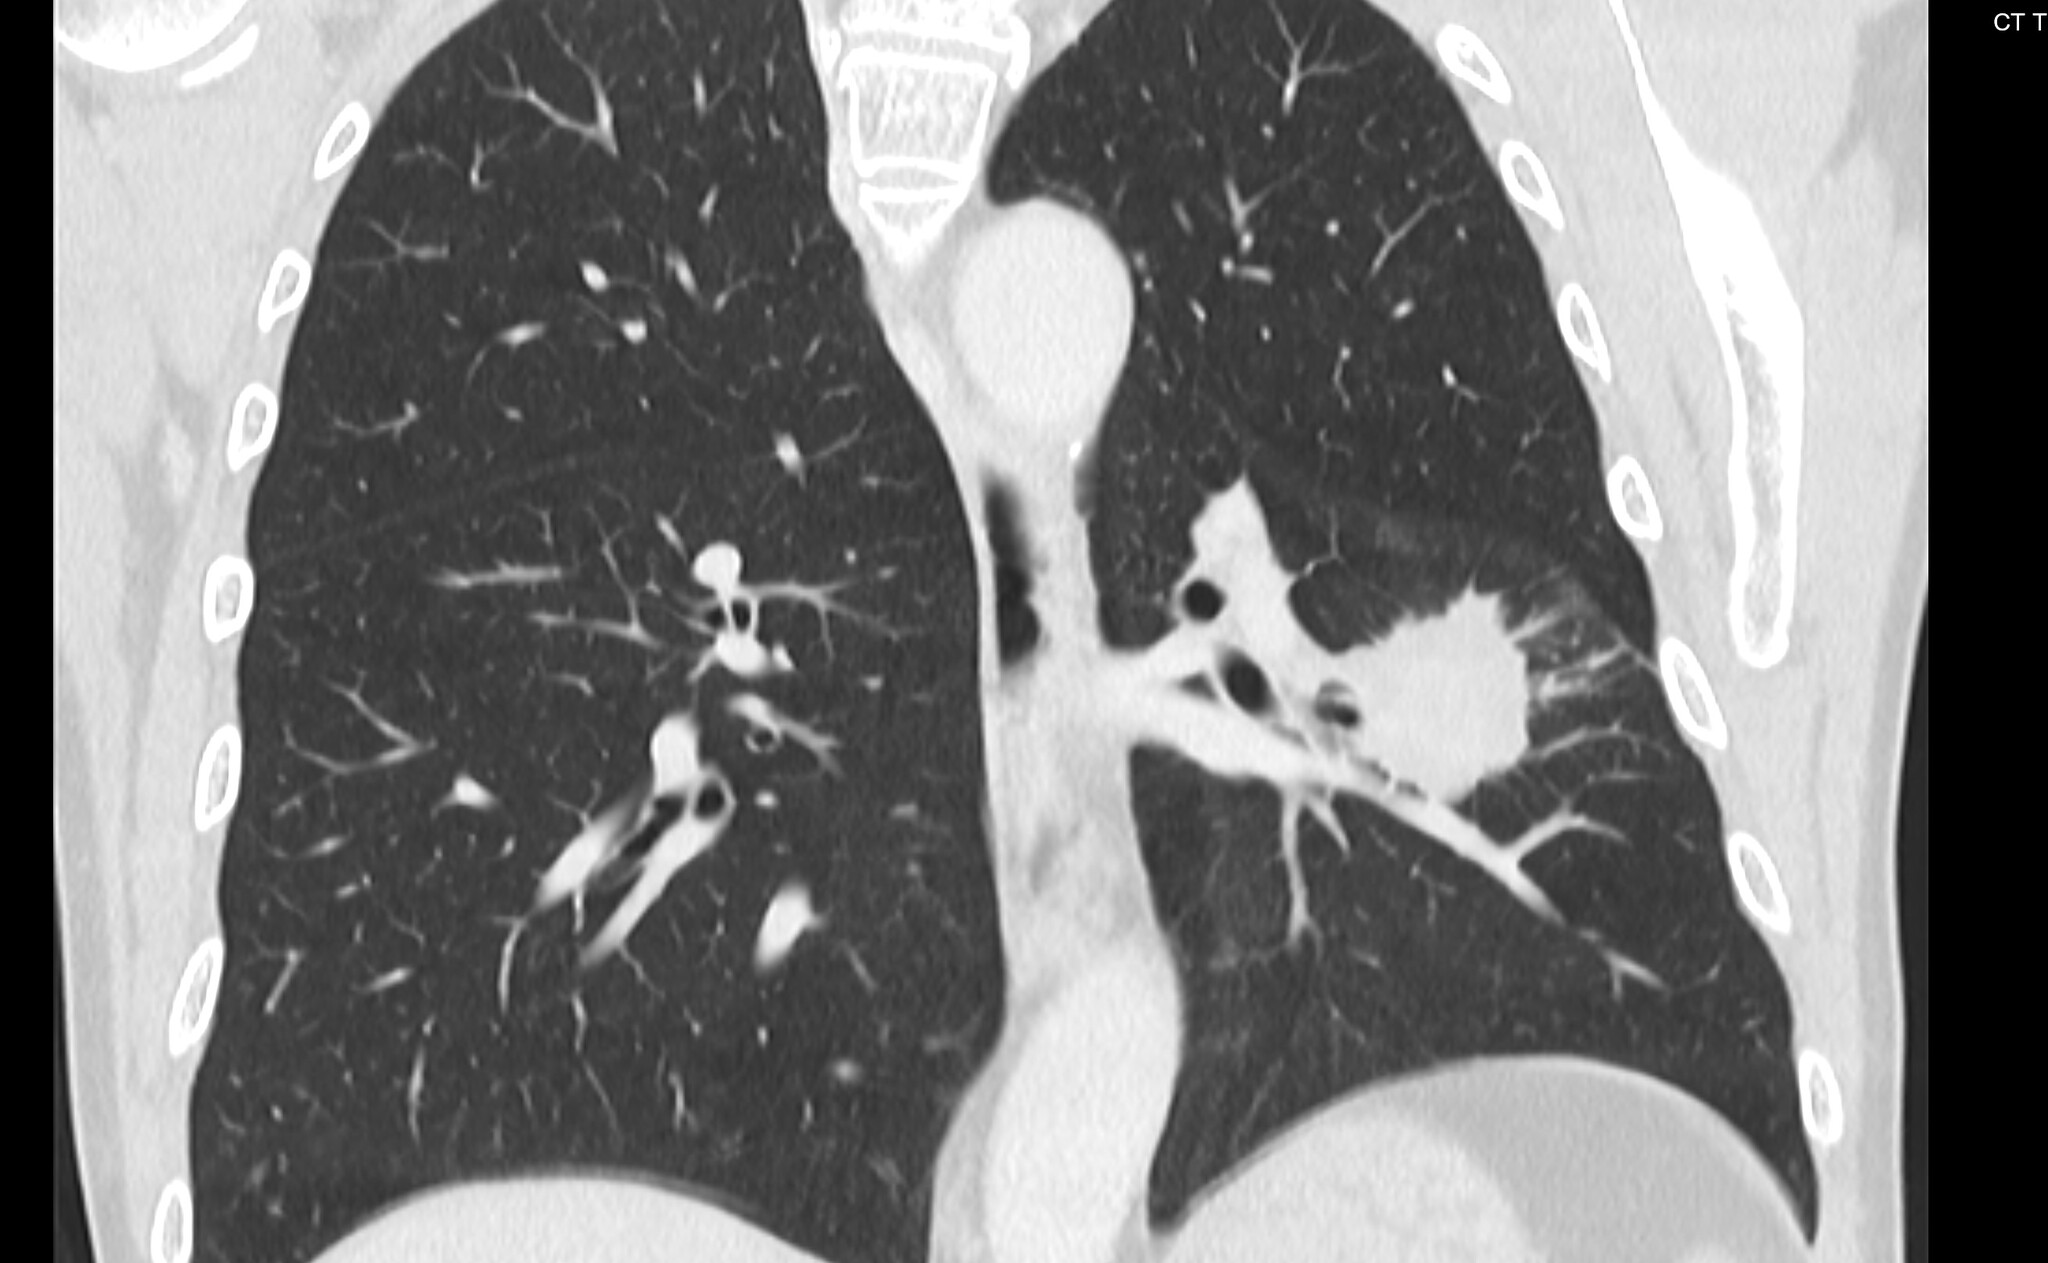

Сегодня мне посчастливилось сделать биопсию лёгкого у мужчины, 68 лет, с подозрением на рак в апикальном сегменте левой нижней доли (на картинках ниже смотрим на правую часть, белое пятно и есть возможное зло). Вроде и образование не шибко маленькое и пункция особых проблем не обещала, но настораживала близость очага к междолевой борозде, которую имелись все шансы повредить, что, статистически, является предпосылкой к пневмотораксу (воздух в плевральной полости):